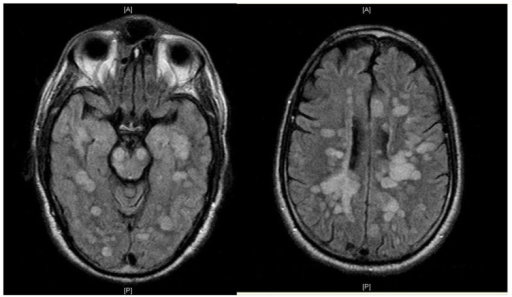

How is ADEM Diagnosed?

ADEM can be difficult to diagnose since its symptoms mimic other neurological conditions.

Key Diagnostic Tests:

- MRI Scan (Brain & Spinal Cord Imaging) – Detects white matter inflammation.